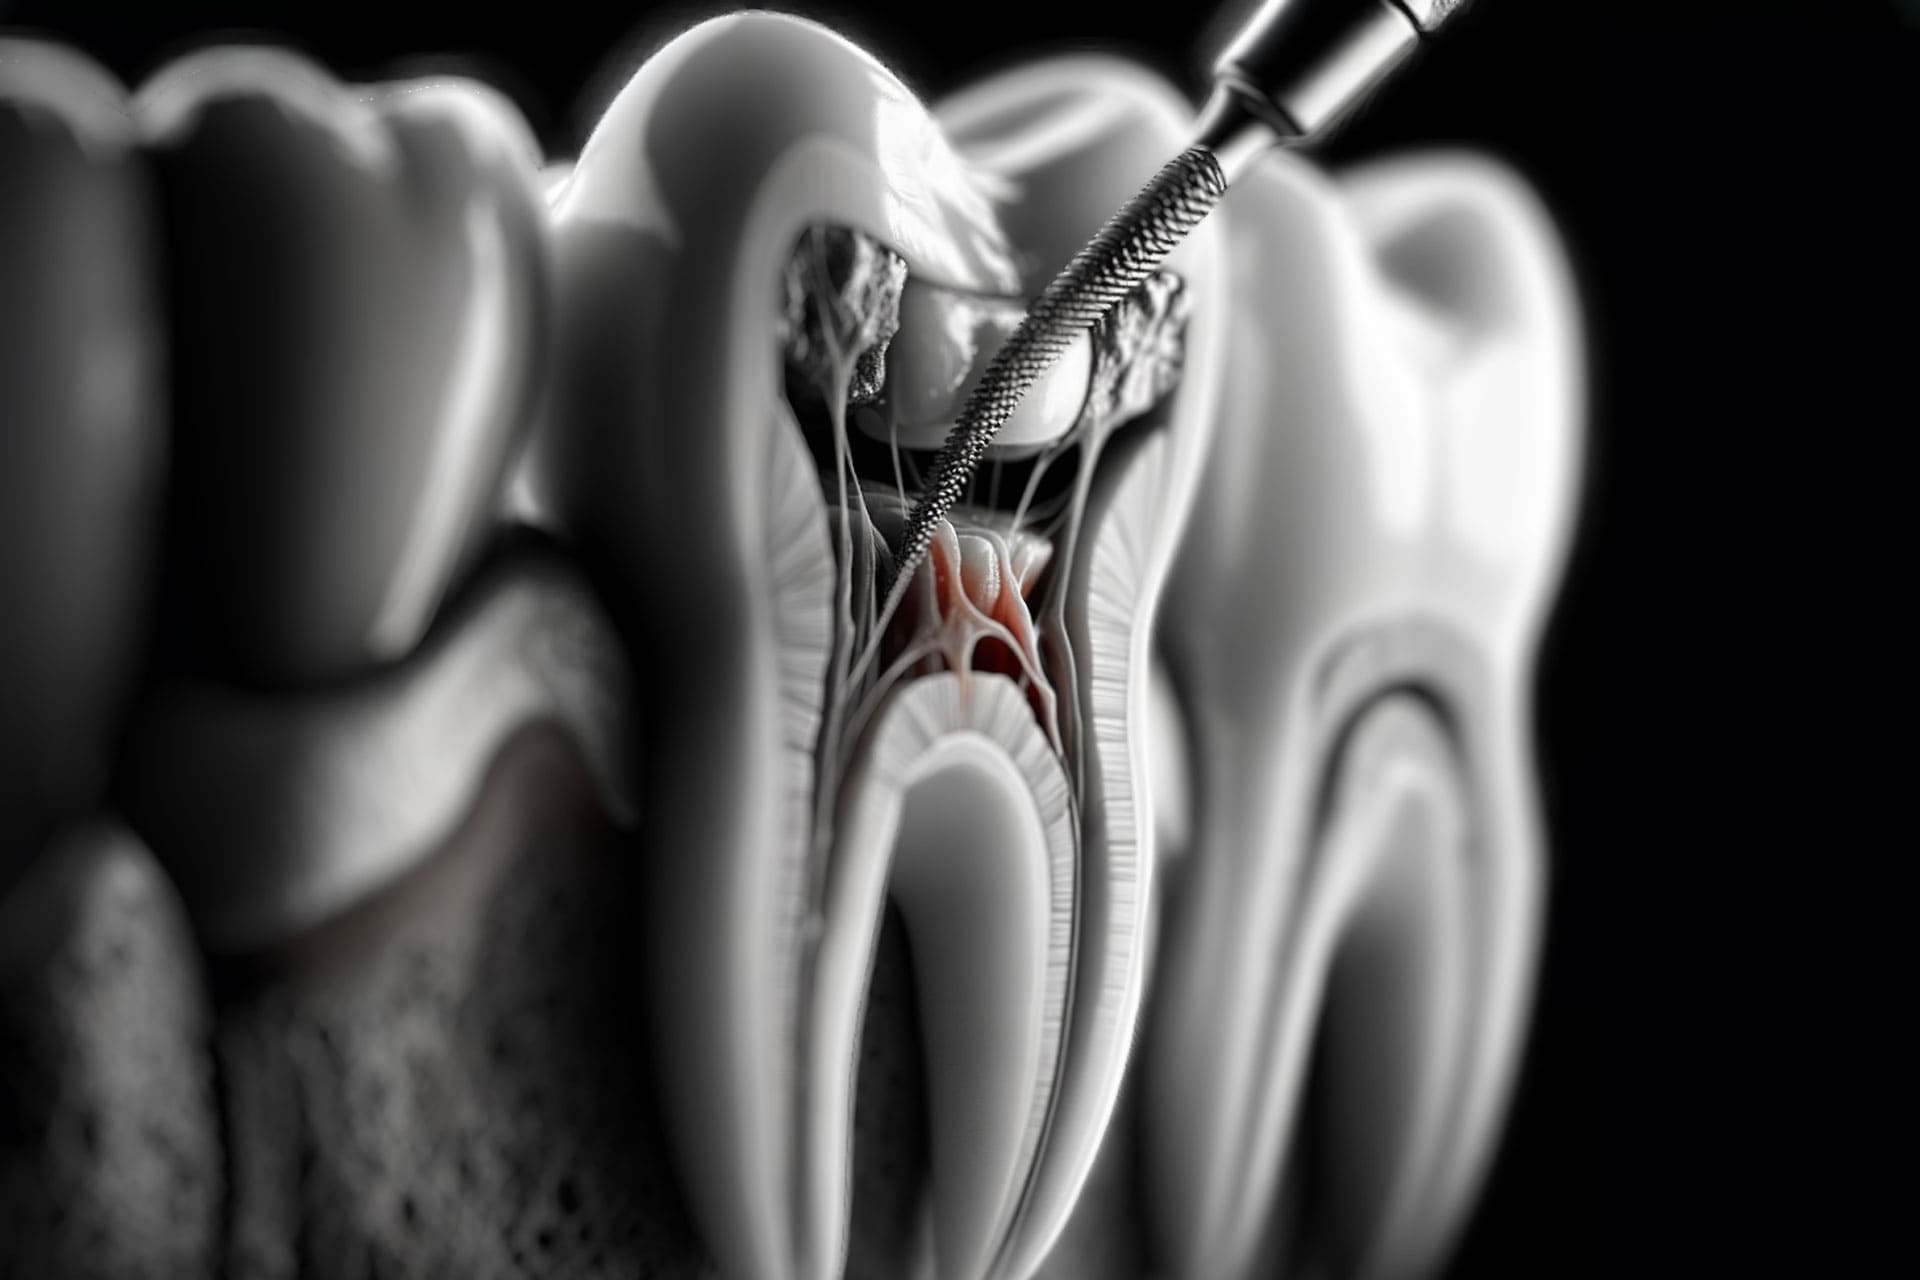

Tedaviler Endodonti Nedir? Endodontik tedavi olarak da bilinen kanal tedavisi en kısa tanımıyla dişin iç kısmında bulunan enfeksiyonun, çürümenin, iltihabın tedavi edilmesi …

- Endodontik diş tedavileri